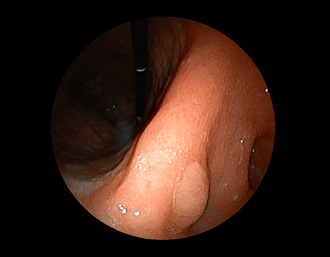

症例2:胃がん(66才男性)

術後胃(B-Ⅱope magen:十二指腸潰瘍手術)。吻合部の後壁側、軽度陥凹の白色病変を認める。生検:Group 5、Signent-ring cell carcinoma(印環細胞癌)と診断[早期胃癌]。高次医療機関へ紹介となり、残胃全摘術(リンパ節郭清)を行いました。